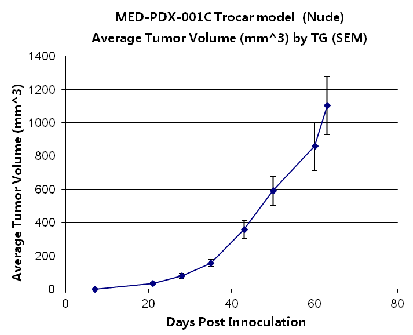

PDX Model (Growth Curve)